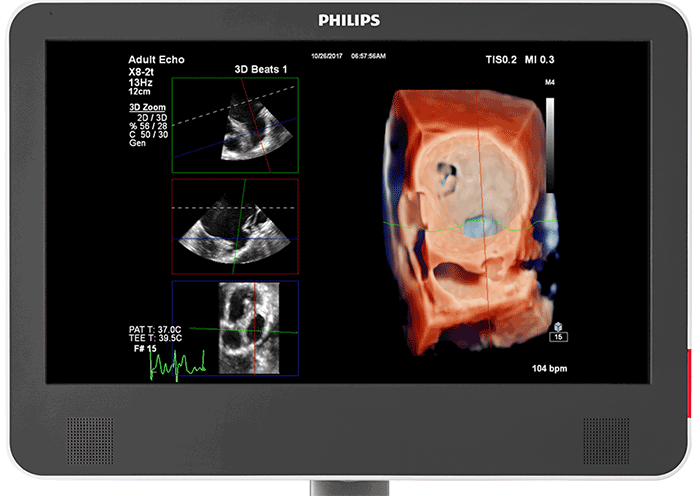

3D photorealistic rendering with virtual light source For improved visualisation of cardiac anatomy in the transthoracic and transesophageal echo, Philips cardiology TrueVue with its virtual light source makes it simpler to visualise the location of defects and comprehend depth within the structures. 90% of clinicians5 who saw the new Philips EPIQ CVx felt that the new TrueVue 3D photorealistic rendering provided improved viewing of anatomical structures, thus increasing clinical confidence.

Designed for next-generation Live 3D TEE The acoustic design of the Philips X8-2t Live 3D transesophageal transducer provides higher frequencies and bandwidth for increased resolution and tissue filling in 2D and Live 3D. It brings true one-beat acquisitions and our highest volume rates in Live 3D and Live 3D colour flow without compromise to image quality. Its handle is designed with a real-time configurable function button allowing for additional functionality while imaging.

Photorealistic rendering built for collaborative intervention suites For better visualisation of interventional devices, Philips cardiology TrueVue, with its virtual light source, is a proprietary and advanced 3D ultrasound display method. TrueVue makes it simpler to visualise the location of catheters and devices by providing images with tissue detail and depth perception. Since it offers a viewing context for the echo images, caregivers in the interventional suite can rely on support when communicating complicated echo images and enhance their procedural confidence. 90% of clinicians5 who saw the new Philips EPIQ CVx felt the new TrueVue 3D photorealistic rendering improved viewing of anatomical structures thus increasing clinical confidence2.

Designed for informative images During an interventional procedure, MultiVue on the Philips EPIQ CVx provides you with one-click cropping of Live 3D